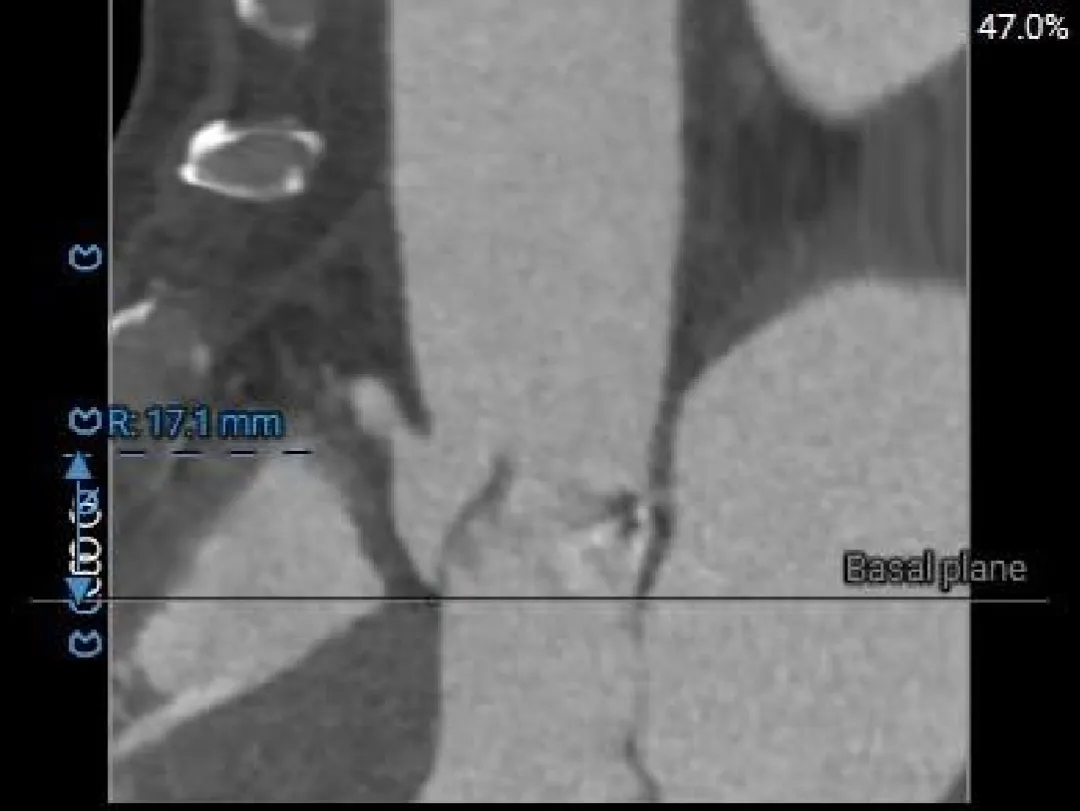

Right Coronary

17.1mm

RCA & Leaflet

16.3mm<19.4mm